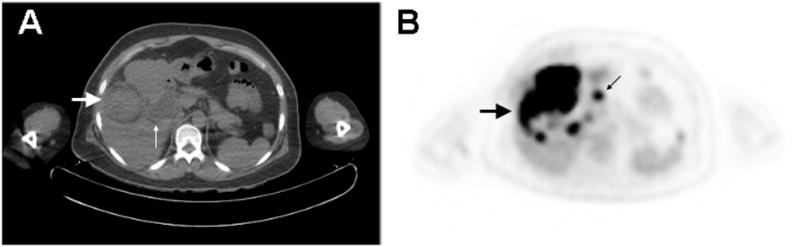

Figure 2.

PET/CT of Neuroendocrine Carcinoma of the Gallbladder. A.) CT image demonstrates a 4.4 cm diameter, intraluminal mass arising from the gallbladder encroaching upon the liver (large arrow). There is associated extra- and intra-hepatic biliary ductal dilatation (small arrow). B.) PET image shows the gallbladder mass to be hypermetabolic, with abnormal metabolism extending into the right hepatic lobe (large arrow). There are also additional discrete hypermetabolic nodules in the right hepatic lobe, as well as hypermetabolic mesenteric and omental lymphadenopathy (small arrow). These findings were consistent with the intraoperative findings of invasive gallbladder carcinoma involving the liver parenchyma as well as regional lymph node metastases.

A few studies have suggested that PET is highly sensitive for detection of GBC (75–100%)20, 25, 27 (Table 3). A case report published by Lin et al28 utilized PET to confirm the diagnosis of neuroendocrine carcinoma of the gallbladder and identify metastatic disease (Figure 2). Other small studies have also supported the potential value of PET in detecting distant metastasis, although given the relatively low prevalence of GBC, there are still insufficient data to establish the overall accuracy of PET for whole-body staging. Nevertheless, PET detected distant metastases in all 7 patients with metastatic GBC in one study20, while another study detected metastases in 3/6 patients with known metastatic GBC25. In a third study, PET was shown to lead to the identification of metastases not seen on other imaging modalities, leading to a change in stage and treatment in 23% (7/31) of patients with GBC24. Butte et al29 also examined the use of PET/CT in 32 patients with GBC incidentally discovered after cholecystectomy and showed a significant difference in mean survival between patients with negative, locally-advanced, and metastatic findings on PET/CT (13.5 vs 6.2 vs 4.9 months, respectively). Thus these studies support the potential clinical and prognostic impact of PET based staging of GBC.